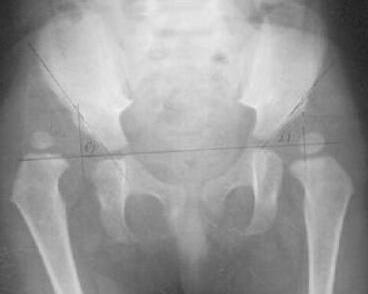

先天性髋关节脱位简称CDH,又称发育性髋关节脱位或发育性髋关节发育不良(DDH)及髋发育不全,是小儿比较常见的先天性畸形之一,股骨头在关节囊内丧失其与髋臼的正常关系,以致在出生前及出生后不能正常发育。以后脱位多见,出生时即存在,女多于男,约6:1,左侧比右侧多一倍,双侧者较少。主要由于髋臼、股骨头、关节囊、韧带和附近肌肉先天性发育不良或异常,导致关节松弛,半脱位或脱位,此外,胎儿在子宫内位置不正常,髋关节过度屈曲,也易致本病,另外遗传因素也较明显。